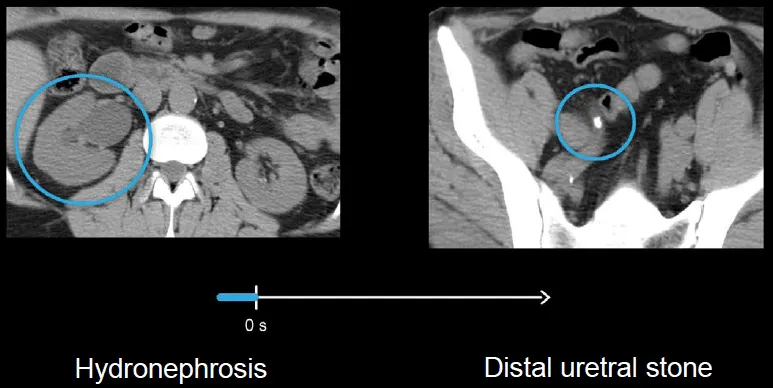

- Non-contrast CT (Abdomen/Pelvis): Gold standard. High sensitivity & specificity.

⭐ Non-contrast helical CT is the single best test for diagnosing acute flank pain suspicious for nephrolithiasis in non-pregnant adults. It identifies stone size, location, and degree of obstruction.